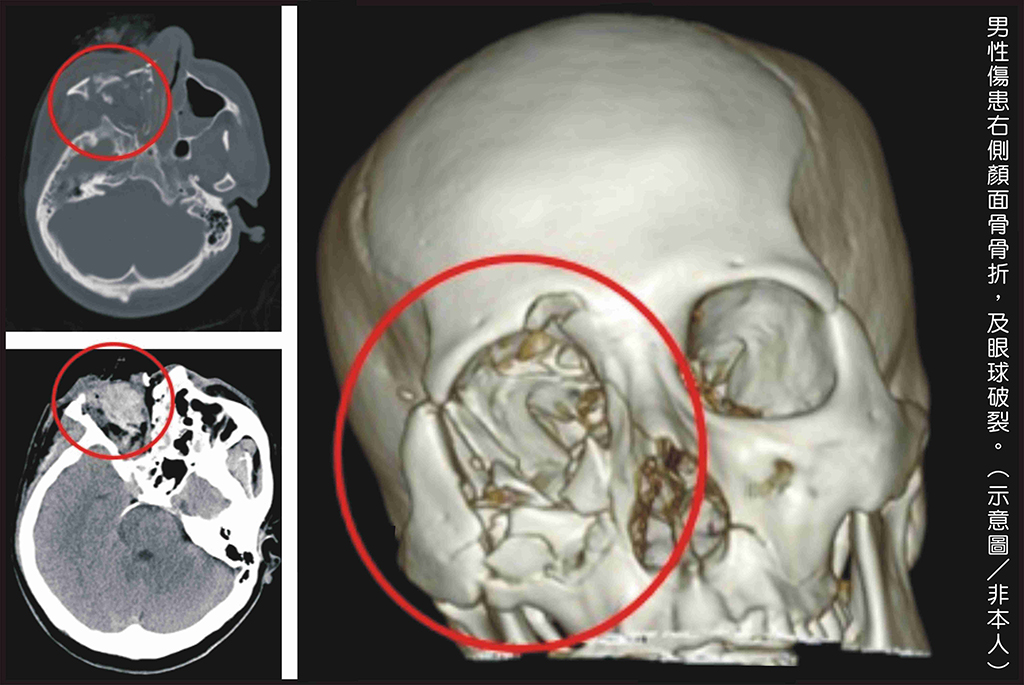

黃勉書醫師表示,男性傷患經檢查顯示嚴重的燒燙傷,右側顏面骨爆裂性骨折、頭骨破裂,合併右眼球破裂。

男性傷患右側顏面骨骨折及眼球破裂。(示意圖/非本人)

日前一名男性,因好奇而把玩鞭炮,輕忽鞭炮爆炸的威力,結果造成永久性無法回復的傷害。當時病人到院時右側臉部血肉模糊,伴隨不斷的哀號。檢查顯示嚴重的燒燙傷而且右側顏面骨爆裂性骨折,頭骨破裂,合併右眼球破裂。彰基醫學中心急診團隊緊急搶救,並匯集眼科、整形外科、神經外科醫師做後續照護,還好病人順利保住性命、意識清楚,穩定治療,後續仍有漫長復原之路。